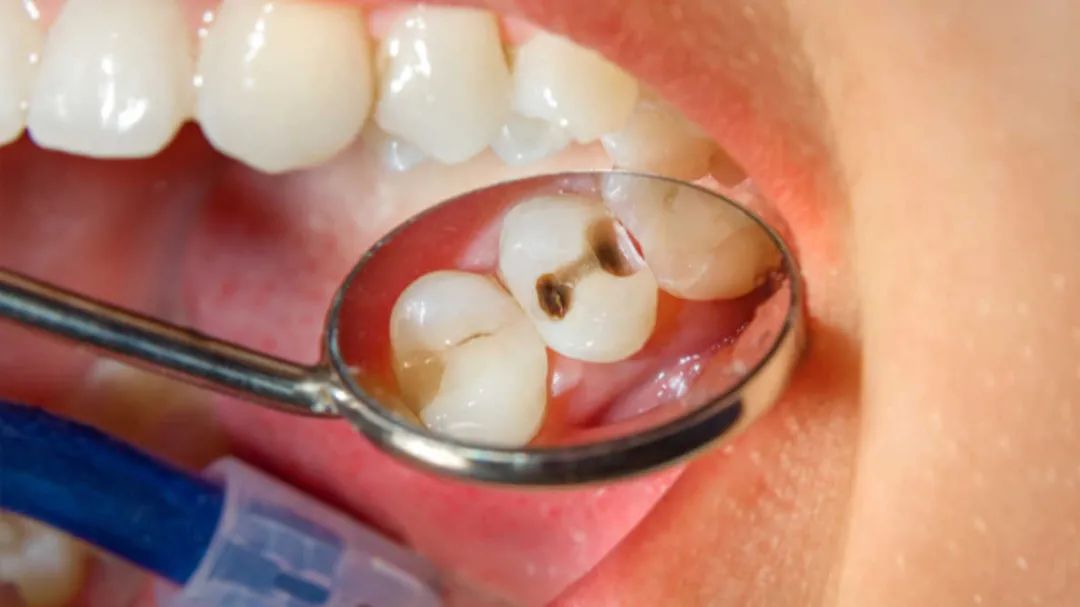

龋齿是世界上最常见、最普遍的慢性疾病。它折磨着九成美国人和全球数十亿人口。但是在过去的30年中,我研究了成千上万种化石和活体动物的牙齿,却几乎看不到任何蛀牙。

当牙釉质出现断裂时,会导致龋齿。富含碳水化合物的饮食会让产酸菌群壮大,从而降低口腔酸碱度。变形链球菌和其他有害细菌在它们喜欢的酸性环境中成长,它们开始淹没有益细菌,进一步降低pH值。临床研究人员将这一系列事件称为营养不良,这意味着口腔环境的生态平衡遭到了破坏,其中少数有害菌种超过了通常在口腔微生物群落中占主导地位的有益菌种。

正因唾液不能足够快地使牙釉质再矿化以保持健康,因此牙齿磨损和修复之间的平衡难以实现。蔗糖(普通糖)尤其是罪魁祸首。有害细菌会利用它形成粘稠的斑块,将其粘结到牙齿上,并存储能量以在两餐之间为它们继续提供能量,这意味着牙齿遭受酸侵害的时间更长。

但是,随着蛀牙的增长,龋齿会淹没这些自然防御力,从而感染牙髓,并从长远来看会杀死牙齿。从进化的角度来看,面对几个世纪人们饮食的迅速变化,以及随之而来的口腔环境变化,牙齿还没有完全适应。